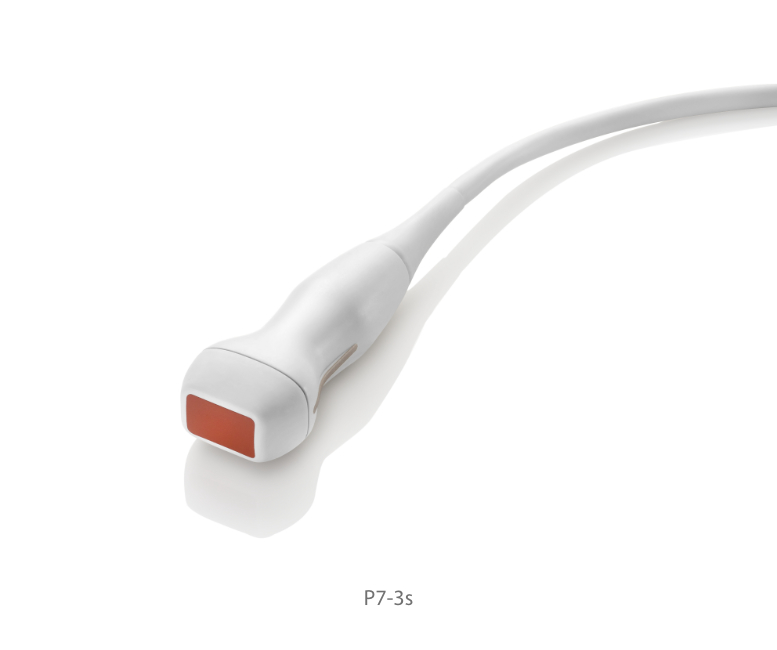

Transducers